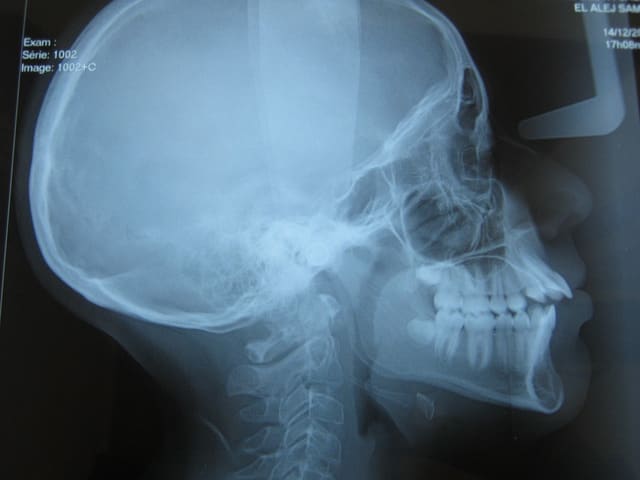

L'examen cephalometrique revele une :

CL1 squelettique

Hyperdivergent

Proalveolie sup et une normoalveolie inf

et une prochelie